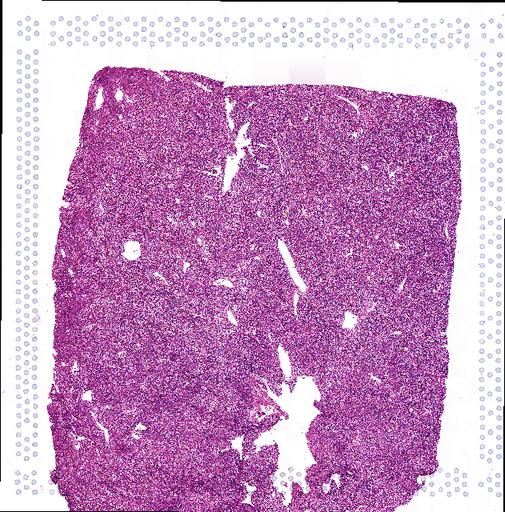

Atlas: Washington University

Identifying tumor-cell-specific markers and elucidating their epigenetic regulation and spatial heterogeneity provides mechanistic insights into cancer etiology. Here, we perform snRNA-seq and snATAC-seq in 34 and 28 human clear cell renal cell carcinoma (ccRCC) specimens, respectively, with matched bulk proteogenomics data. By identifying 20 tumor-specific markers through a multi-omics tiered approach, we reveal an association between higher ceruloplasmin (CP) expression and reduced survival. CP knockdown, combined with spatial transcriptomics, suggests a role for CP in regulating hyalinized stroma and tumor-stroma interactions in ccRCC. Intratumoral heterogeneity analysis portrays tumor cell-intrinsic inflammation and epithelial-mesenchymal transition (EMT) as two distinguishing features of tumor subpopulations. Finally, BAP1 mutations are associated with widespread reduction of chromatin accessibility, while PBRM1 mutations generally increase accessibility, with the former affecting five times more accessible peaks than the latter. These integrated analyses reveal the cellular architecture of ccRCC, providing insights into key markers and pathways in ccRCC tumorigenesis.